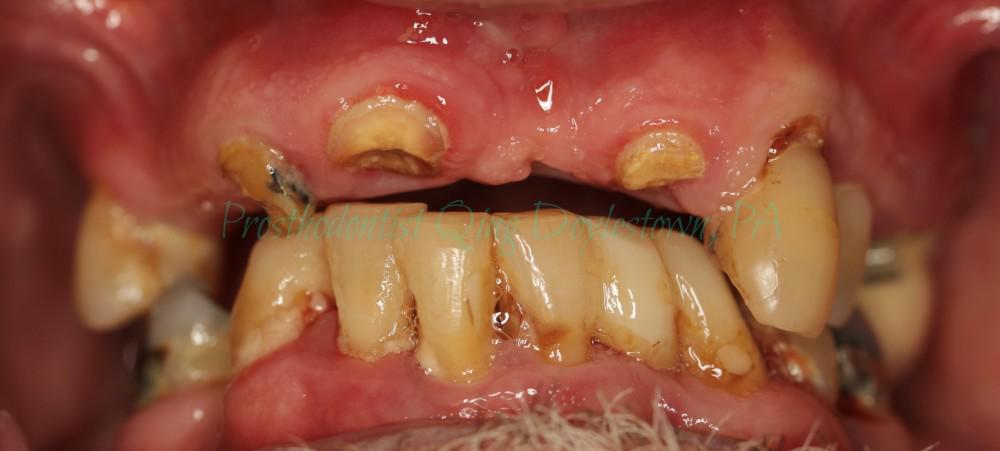

Restore smile , Restore ego ! Patient came with Stage 4 Grade C severe periodontitis.

Front teeth broke and his removable partial denture also broke which needs denture repair.

After an accurate diagnosis, thorough periodontal treatment and save all possibly save able teeth, Prosthodontist Qing team accomplished the challenging case by giving the patient functional and esthetics rehabilitation including upper hopeless teeth extraction, immediate complete denture, lower hopeless teeth extraction, periodontal treatment of the gum disease, guided tissue regeneration, and dental bridges.